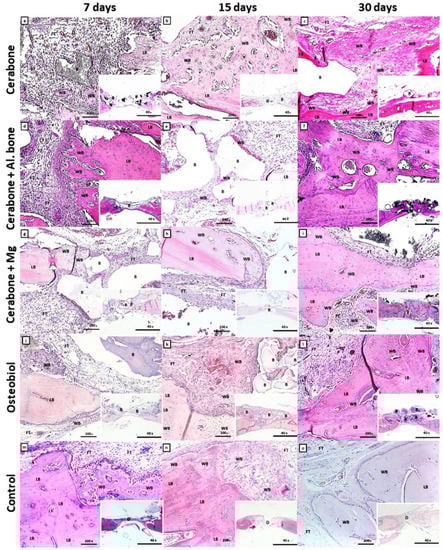

2.2. Histology and Immunohistochemistry